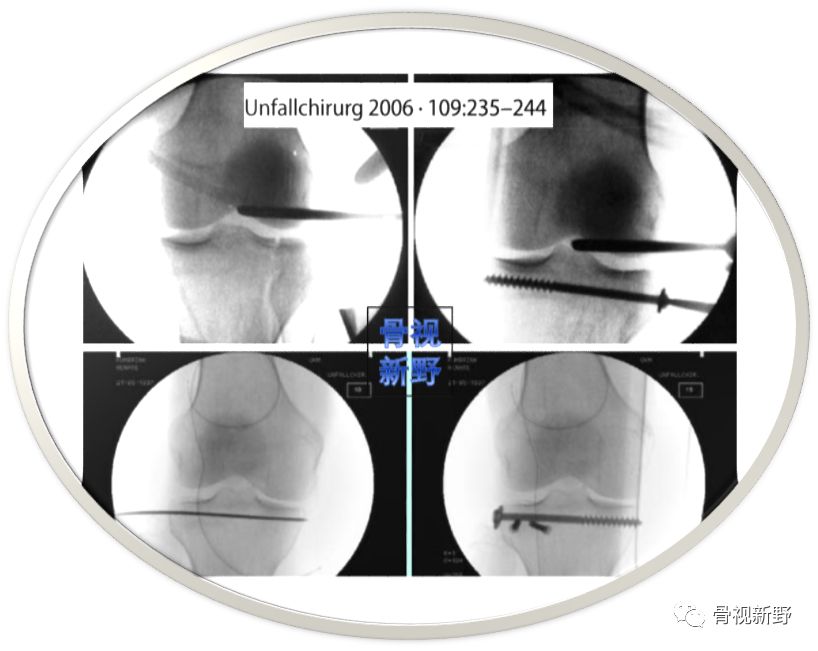

早在2006年,Petersen W 等即有类似应用报道(原文是德文)。

2013年,Weinmann 等人正式提出 “ 栅栏螺钉”技术(Jail screw technique)这个名称,并与“平行螺钉”固定进行了固定强度的比较研究。

“ 栅栏螺钉”技术(Jail screw technique)的理念是在常规软骨下骨平行螺钉(排钉)下方再紧挨着加打1-2枚垂直螺钉的固定技术。